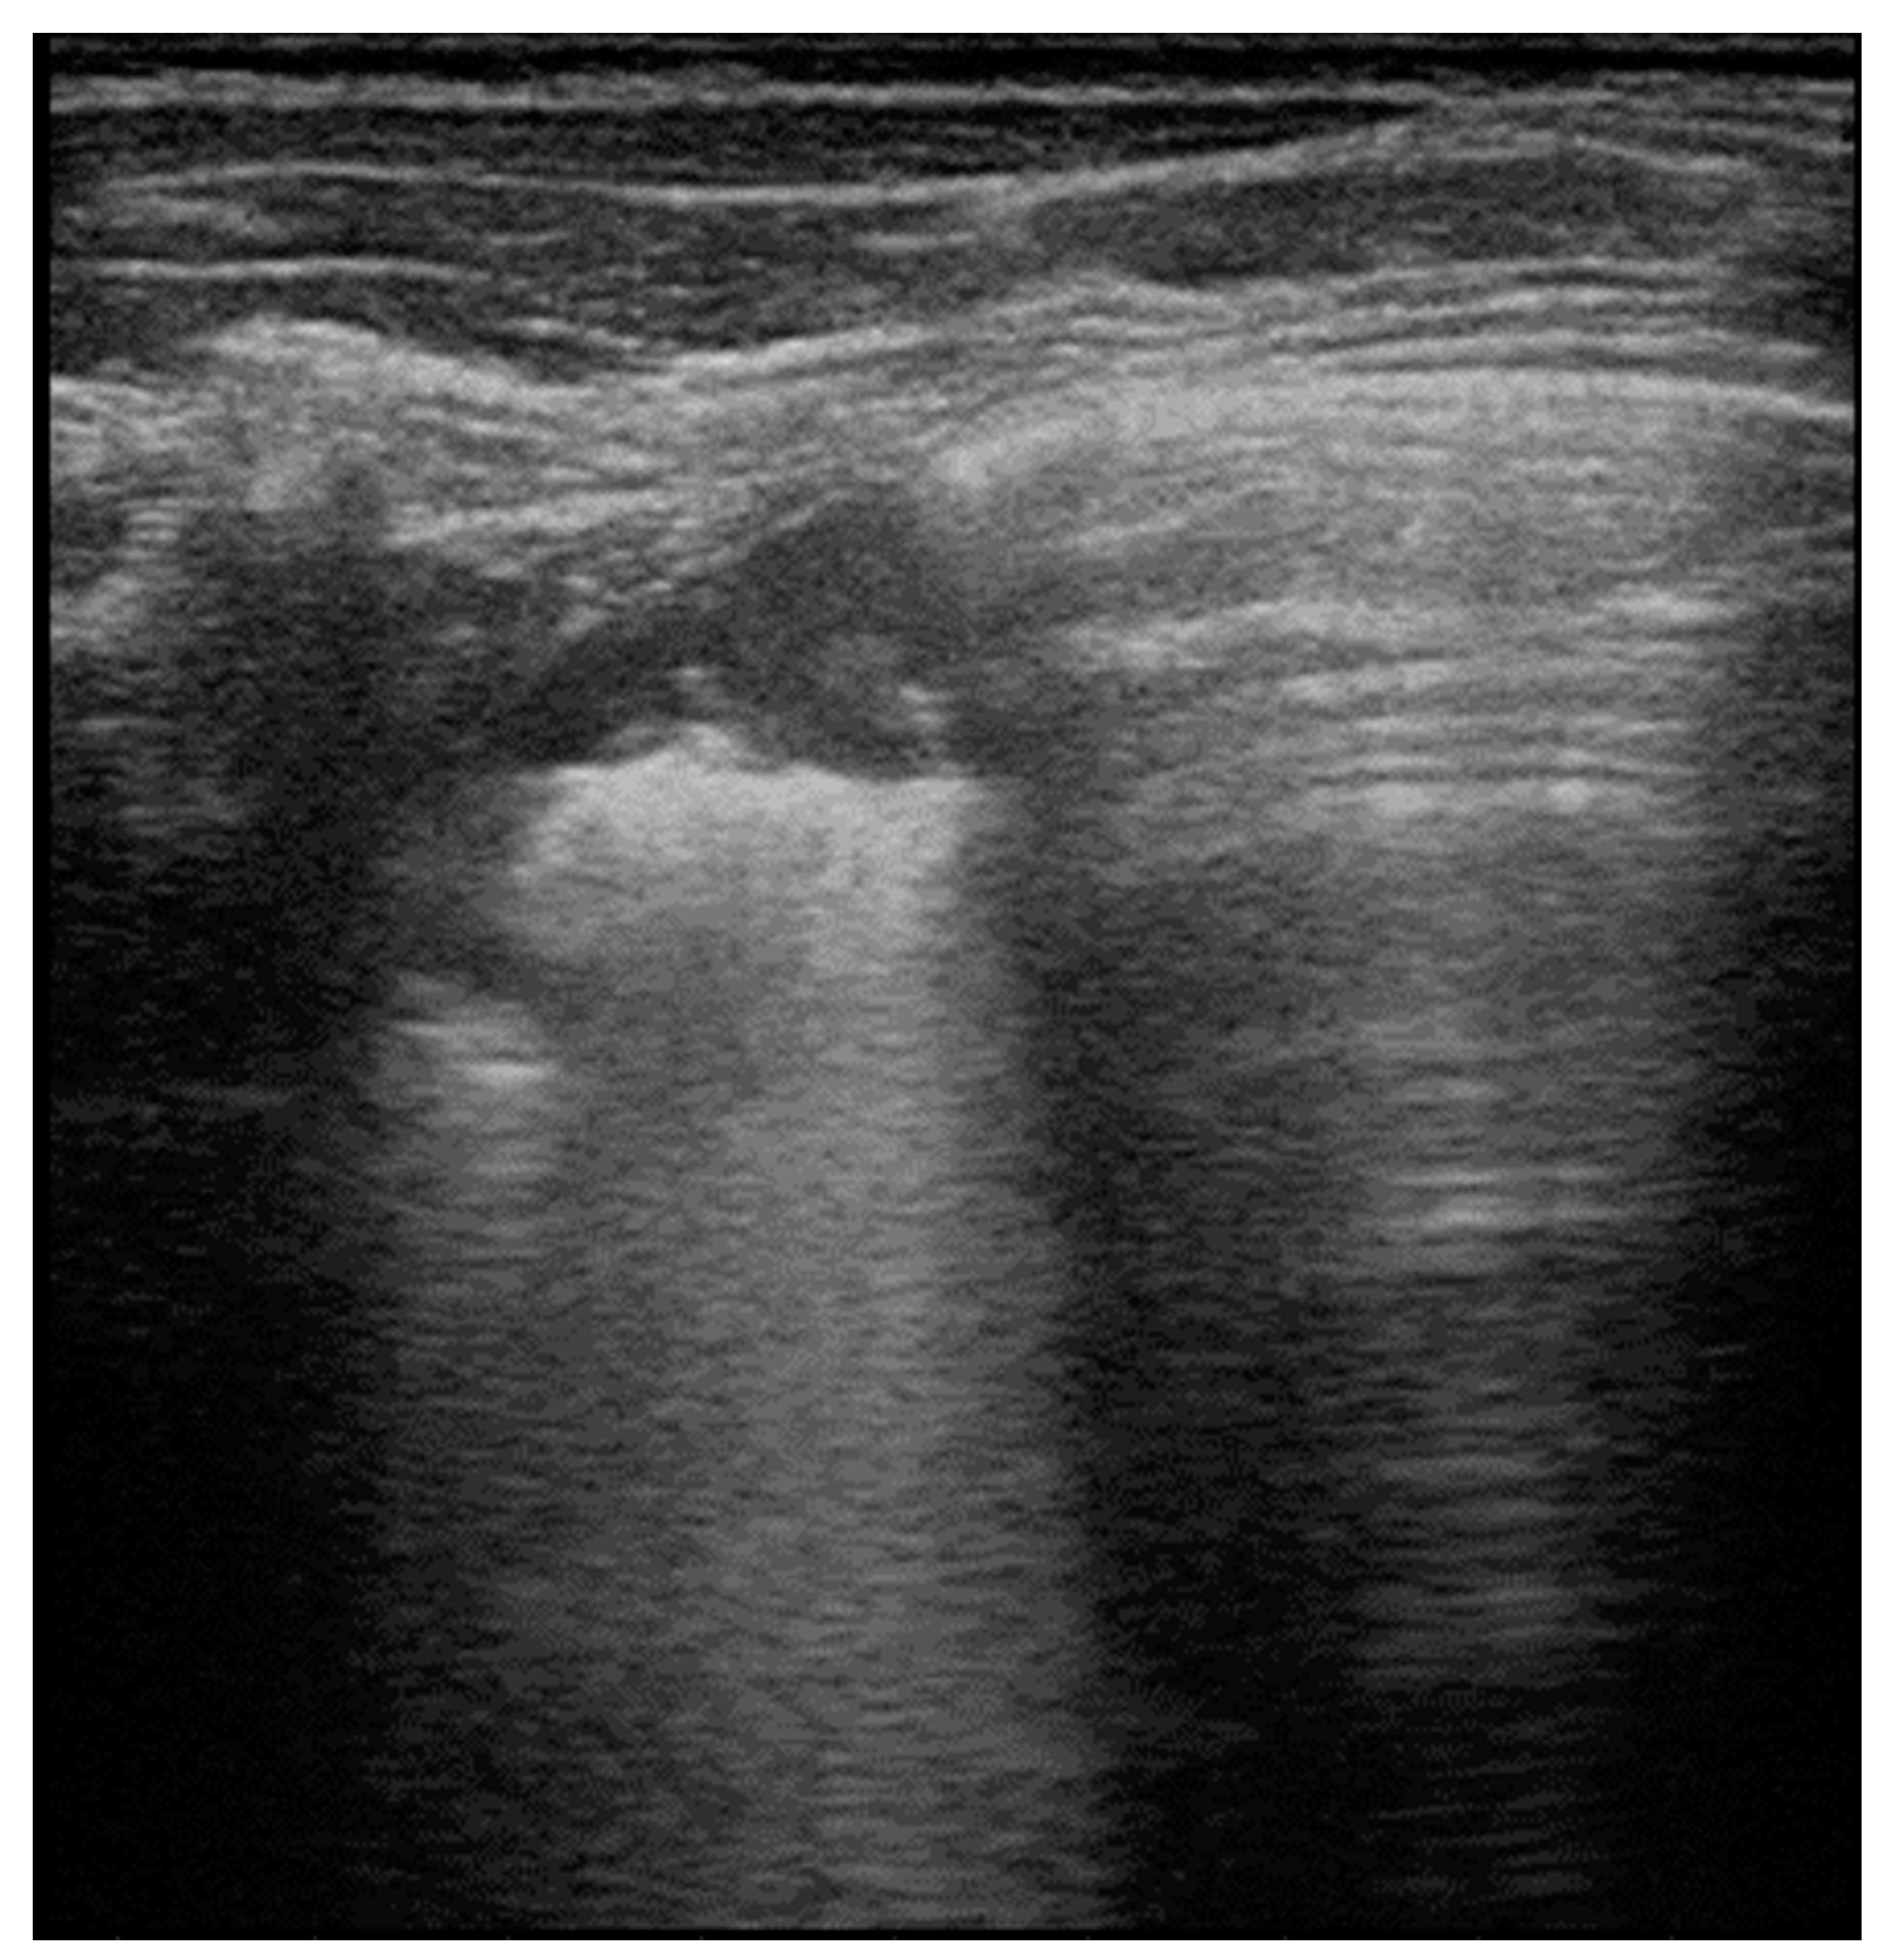

4.3. Pneumonia

4.4. Atelectasis